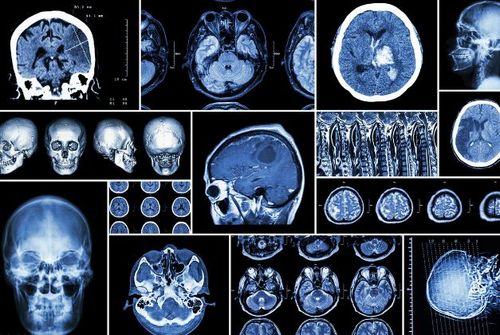

影像医生必须掌握的头颅ct解剖与常见出血梗死判读

正常头颅ct图片

正常头颅ct解剖图

头颅ct图片

头颅ct图解

头颅ct怎么看图解

头颅ct解剖图

头颅CT解剖图谱

头颅CT断层解剖图

头颅ct断层解剖讲解